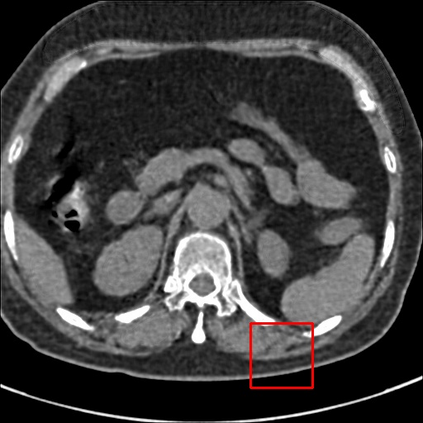

Low-Dose Computed Tomography (LDCT) technique, which reduces the radiation harm to human bodies, is now attracting increasing interest in the medical imaging field. As the image quality is degraded by low dose radiation, LDCT exams require specialized reconstruction methods or denoising algorithms. However, most of the recent effective methods overlook the inner-structure of the original projection data (sinogram) which limits their denoising ability. The inner-structure of the sinogram represents special characteristics of the data in the sinogram domain. By maintaining this structure while denoising, the noise can be obviously restrained. Therefore, we propose an LDCT denoising network namely Sinogram Inner-Structure Transformer (SIST) to reduce the noise by utilizing the inner-structure in the sinogram domain. Specifically, we study the CT imaging mechanism and statistical characteristics of sinogram to design the sinogram inner-structure loss including the global and local inner-structure for restoring high-quality CT images. Besides, we propose a sinogram transformer module to better extract sinogram features. The transformer architecture using a self-attention mechanism can exploit interrelations between projections of different view angles, which achieves an outstanding performance in sinogram denoising. Furthermore, in order to improve the performance in the image domain, we propose the image reconstruction module to complementarily denoise both in the sinogram and image domain.